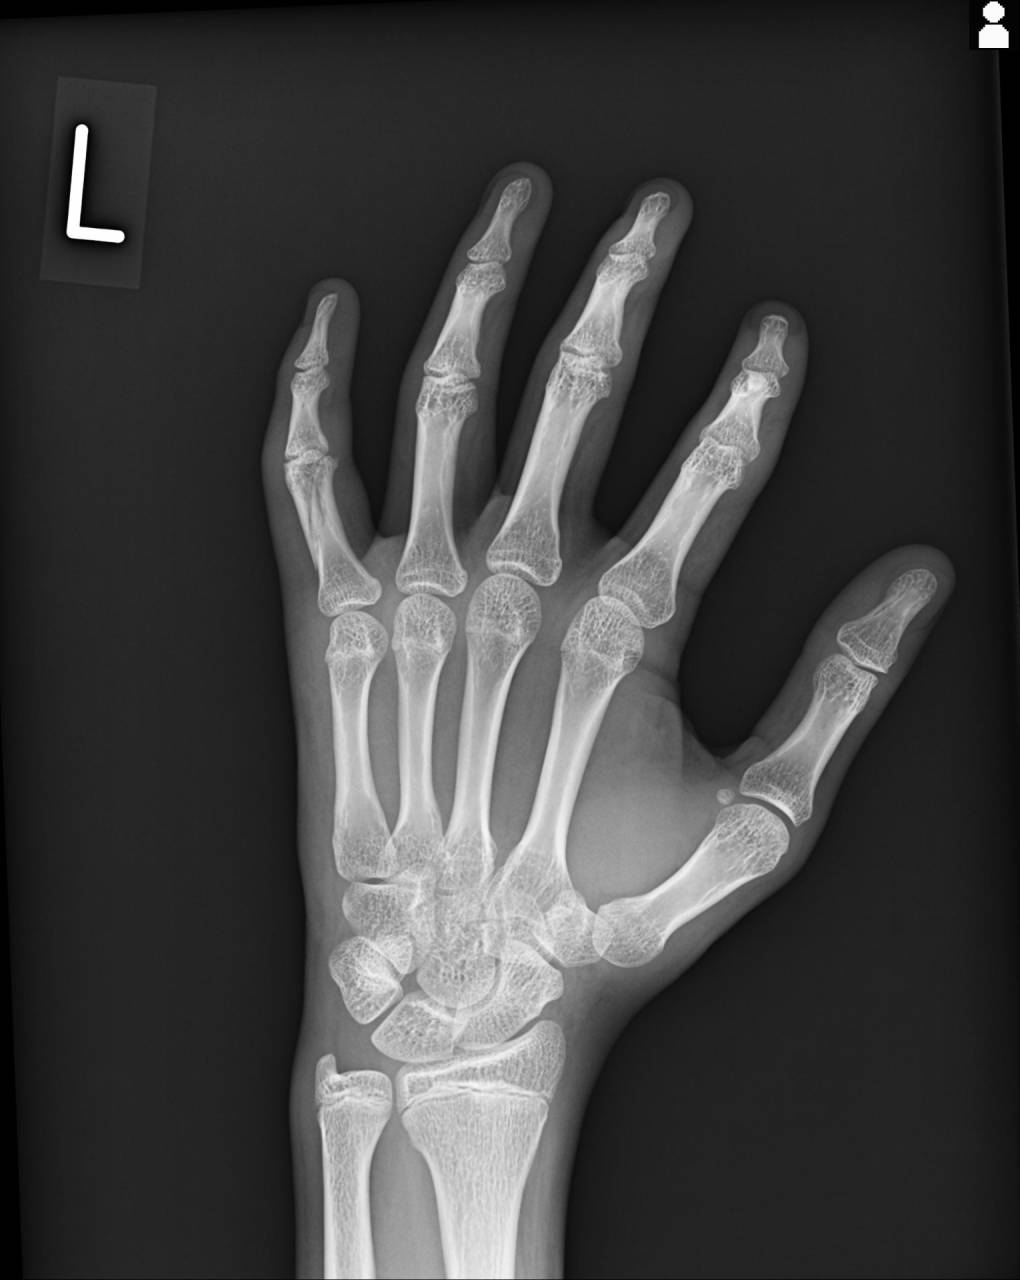

第5指基節骨に骨折線が確認できたので、当整骨院が提携させてもらってる病院にてレントゲン検査の依頼をし撮影してもらいました。

撮影した画像を確認すると、左第5指基節骨斜骨折で病院の先生も手術適応になるものとのことで、大怪我です。

今回の症例は基節骨が斜めに折れていて、背側・外側・短縮転位をしているため整復を行う必要があると同時に固定で転位しないようにしなくてはいけません。

さらに正しく整復・固定を行わないと、骨が修復し、いざ指を曲げようとした時に指同士が重なってしまったり、屈曲に支障が出てくる可能性があるので気をつけてやらねばいけません。

レントゲン画像とエコーを使いながら整復を行います。